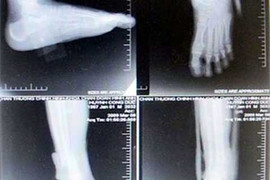

Một thanh niên 27 tuổi vừa phải phẫu thuật cắt bỏ chân phải sau tai nạn được chẩn đoán là bong gân tại Bệnh viện Chấn thương chỉnh hình TP.HCM.